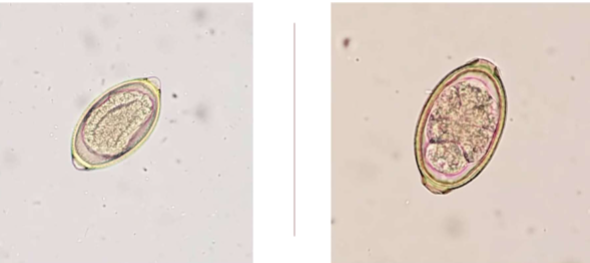

Aelurostrongylus abstrusus

feline lungworm

what does Aelurostrongylus abstrusus infect

cats

where is Aelurostrongylus abstrusus located in host

respiratory bronchioles

what techniques can you use to diagnose Aelurostrongylus abstrusus

fecal float and baermann technique (b is more reliable)

is Aelurostrongylus abstrusus zoonotic

no

Pearsonema plica/ Pearsonema feliscati

bladder worm of dogs, foxes, and cats

what lifecycle does Pearsonema plica/ Pearsonema feliscati have

indirect; earthworm is the intermediate host

symptoms of Pearsonema plica/ Pearsonema feliscati

usually asymptomatic, but can cause blood in urine, irritated bladder